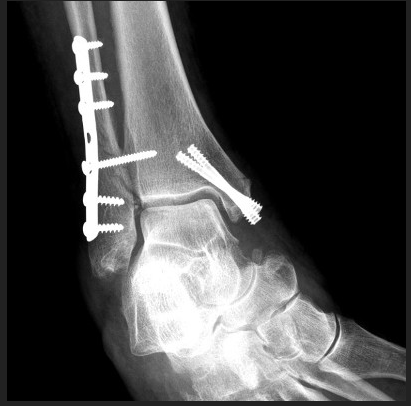

Остеосинтез ортопеды

Остеосинтез ортопеды 113 фото